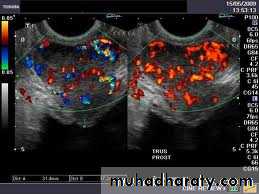

Transrectal Ultrasound ( TRUS ) + Biopsy